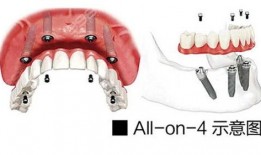

爆料种植牙套路视频播放,视频曝光惊人内幕

你知道吗?最近网上有个视频,火得一塌糊涂,那就是关于种植牙的“套路”揭秘。这可真是让人大开眼界,今天就来给你好好聊聊这个话题。一...